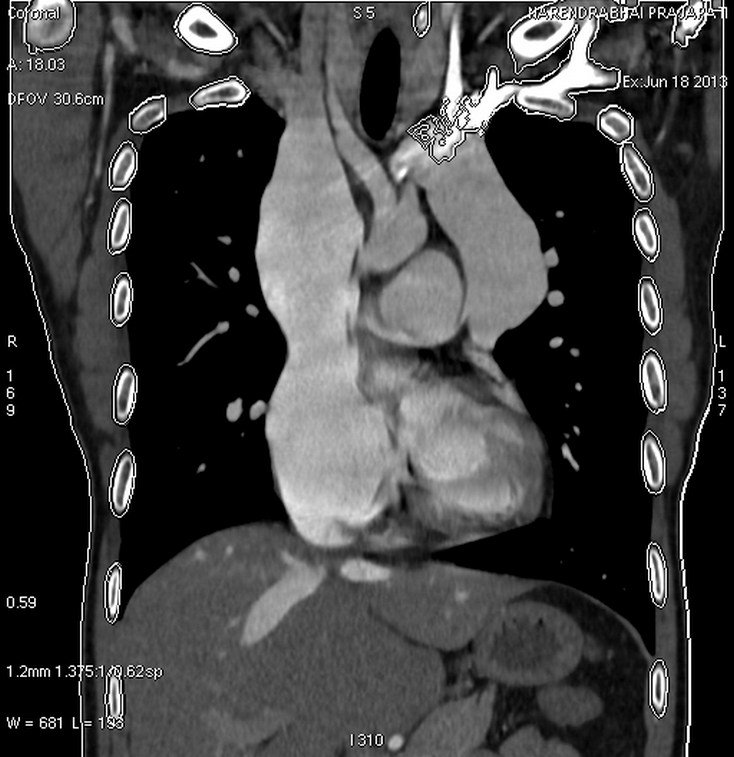

CT Kidney

Kidney Angiography